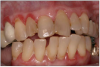

Periodontal Disease (Figure 11). To quote the 2014 Surgeon General's report, "The evidence is sufficient to infer a causal relationship between smoking and periodontitis."2 This was highlighted by Tomar and Asma, when they showed that 52.8% (8.1 million people) of periodontitis in the US population was attributable to current and former smokers.31 In addition, it was also demonstrated that quitting smoking reduced the risk of periodontitis.8,34

Figure 11. Periodontal disease.

Figure 11